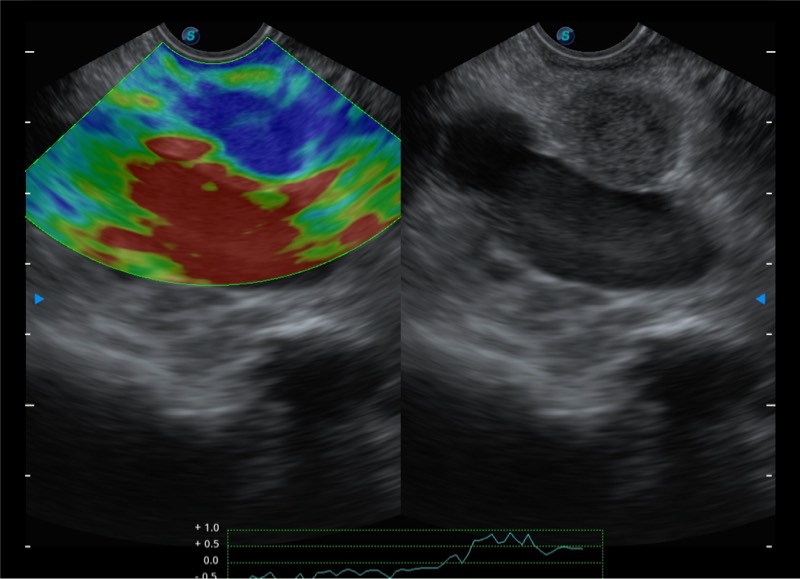

基于二十年的超声技术积累,哈哈体育官网提供了最新一代的独立超声主机,在提供高质量图像的同时满足多学科使用。具备常见多普勒技术并提供弹性成像、声学造影等高端影像技术。新一代传感器具有更强的抗干扰能力并减少图像伪影。

• 4-12MHZ宽频输出